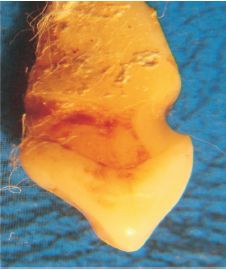

Fig. 2 Lesión cóncava en forma de cuchara.

Asociada clásicamente a abrasión